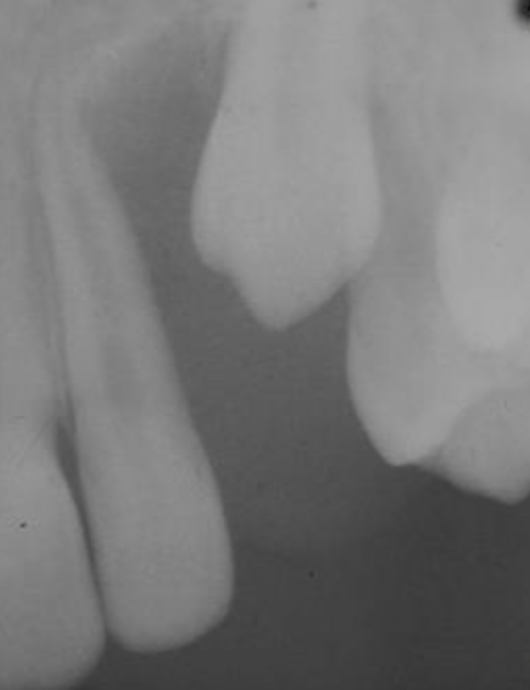

Q

A

eruption cyst

15

16